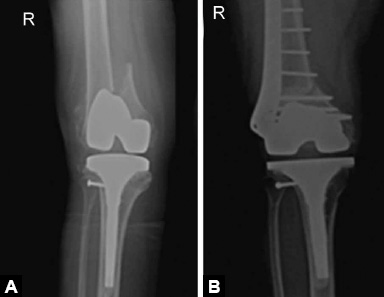

Fractures around joint replacement prostheses are called periprosthetic fracture. These usually result from low energy fall. Patients present with pain around prosthesis and difficulty in weight bearing following a fall. Diagnosis is made on X-rays (Figs. 1.51A and B).

Figs. 1.51A and B: X-ray knee AP view showing periprosthetic distal femoral fracture around total knee arthroplasty and its management with ORIF with distal femoral locked plate.

Treatment of these fractures is challenging due to poor bone stock and presence of prosthesis poses difficulty in internal fixation. Displaced fractures with stable prosthesis are usually treated with ORIF with locking plates. Loose prosthesis needs to be replaced by revision arthroplasty.